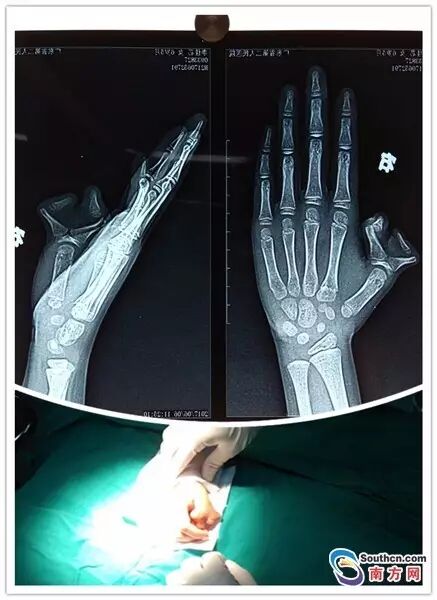

近日,广东省第二人民医院整形美容中心就收治了一名有着“蟹钳”手的小女孩朵朵(化名)。老家在汕头的朵朵今年6岁,出生时右手拇指就是多指畸形,拇指有主、副两个,状似蟹钳。

右手拇指长肉团长成“蟹钳指”

朵朵是广东汕头人,在她出生后,家长就发现朵朵右手拇指根部多出一块肉团,随着时间的推移,肉团逐渐长成一个“小拇指”,和“大拇指”就像一个螃蟹钳上的两个夹子。

据王绥江介绍,多指手术不是简单的切除多余手指,而是要兼顾手部外观的改善和手功能的重建。朵朵的多指畸形伴有骨和关节畸形,目前,朵朵已经接受了多指切除和骨关节矫正手术,术后须予以固定,并及时去除固定和开始功能锻炼。

多指的手术切除并不困难,但需根据赘生指的外形、位置并结合X线检查以明确其结构及与其正常手指的关系作全面考虑来决定多指切除的部位和方式